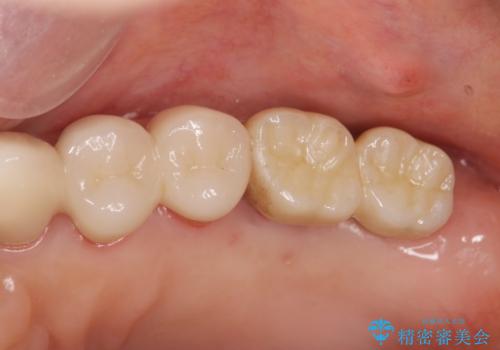

歯周病に対する全体治療

- 近医で「重度の歯周病です、入れ歯にする必要がある。」、と言われ入れ歯以外の方法がないか相談にみえられました。

再生治療、歯周外科を行うことで歯周病治療を行い、残すことのできる歯の歯周環境を整える。

残すことのできない歯は抜去したのち骨造成を含めたインプラント治療を行い、しっかりとした咬合関係を確立していきます。

治療期間はかかりましたが、しっかりと歯周病治療・インプラント治療を行ったおかげで歯周病の状態は非常に良くなり、安定した咬合関係を確立することができました。